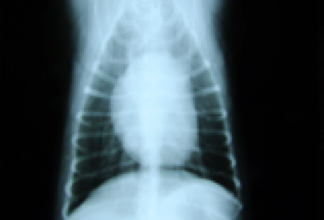

Das Röntgen

Bein Röntgenaufnahmen des Brustkorbes werden das Herz, die Lunge, die großen Blutgefäße, das Zwerchfell und Skelett dargestellt. Mit dieser Übersicht kann der Kardiologe eine Herz- oder Lungenerkrankung (z.B. Lungenödem – also Wasser in der Lunge, Stauungen der Blutgefäße), Lungenentzündungen, Tumore und eine Herzvergrößerung erkennen.

Herz eines Hundes in der v/d Aufnahme